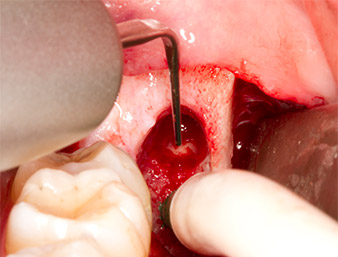

Using an instrument for periodontal debridement (Piezomed P1), the periodontal ligament space of the radix relicta was then widened minimally (Fig. 8).

The same activated instrument was inserted into the root canal and loosened the fragment as a result of its micro-oscillating vibrations (Fig. 9, 10).

Piezomed P1

Fig. 9: The Piezomed P1 instrument is recommended by the manufacturer primarily for periodontal debridement but is also suitable for surgical purposes. Here it is placed in the root canal after minimal widening of the periodontal ligament space.

Fig. 10: Due to its slender shape, the instrument can penetrate the root canal and remove the root remnant by means of micro-oscillation (vibration).